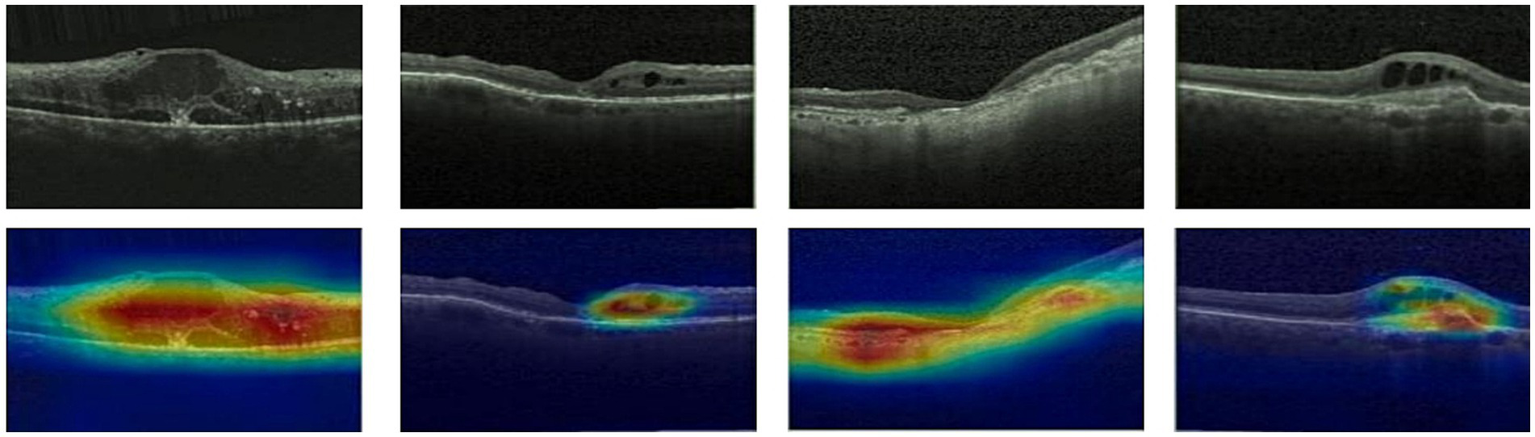

3.4 Features map visualization

Given ethical considerations and direct impact on human life and health, the interpretability of deep learning models could help clinicians, patients, and researchers in comprehending, trusting, and efficiently employing artificial intelligence technologies in the healthcare domain. In this section, we utilized the Grad-CAM method (38) to present Class Activation Mapping (CAM) visualizations, which could demonstrate the evidence underlying the predictions of the proposed model. The heat maps were generated by the CAM technique to emphasizes specific regions in an OCT image that were closely linked to the target class. The Grad-CAM showed the regions of interest. As shown in Figures 8, 9, 10, the Grad-CAM were generated based on original OCT images. Deeper red color represented stronger correlation with the predicted category. From the Grad-CAM, we found that the lesion regions were all appear with red. It demonstrated that the model payed attention to the crucial regions, which aligned with the diagnostic process of ophthalmologists.

Figure 8

Features map visualization of HyReti-Net on OCT-2014 dataset. The first line is the original OCT images. The second line is class activation mapping visualizations based on Grad-CAM method.

For each public dataset, heatmaps were also generated to enhance the interpretability of OCT image classification, as shown in Figures 8, 9, 10. The heatmaps showed the specific regions in an OCT image that were closely linked to the target class. It meant that HyReti-Net was able to accurately focus on the lesion area, which meant that the corresponding classification performance was better.